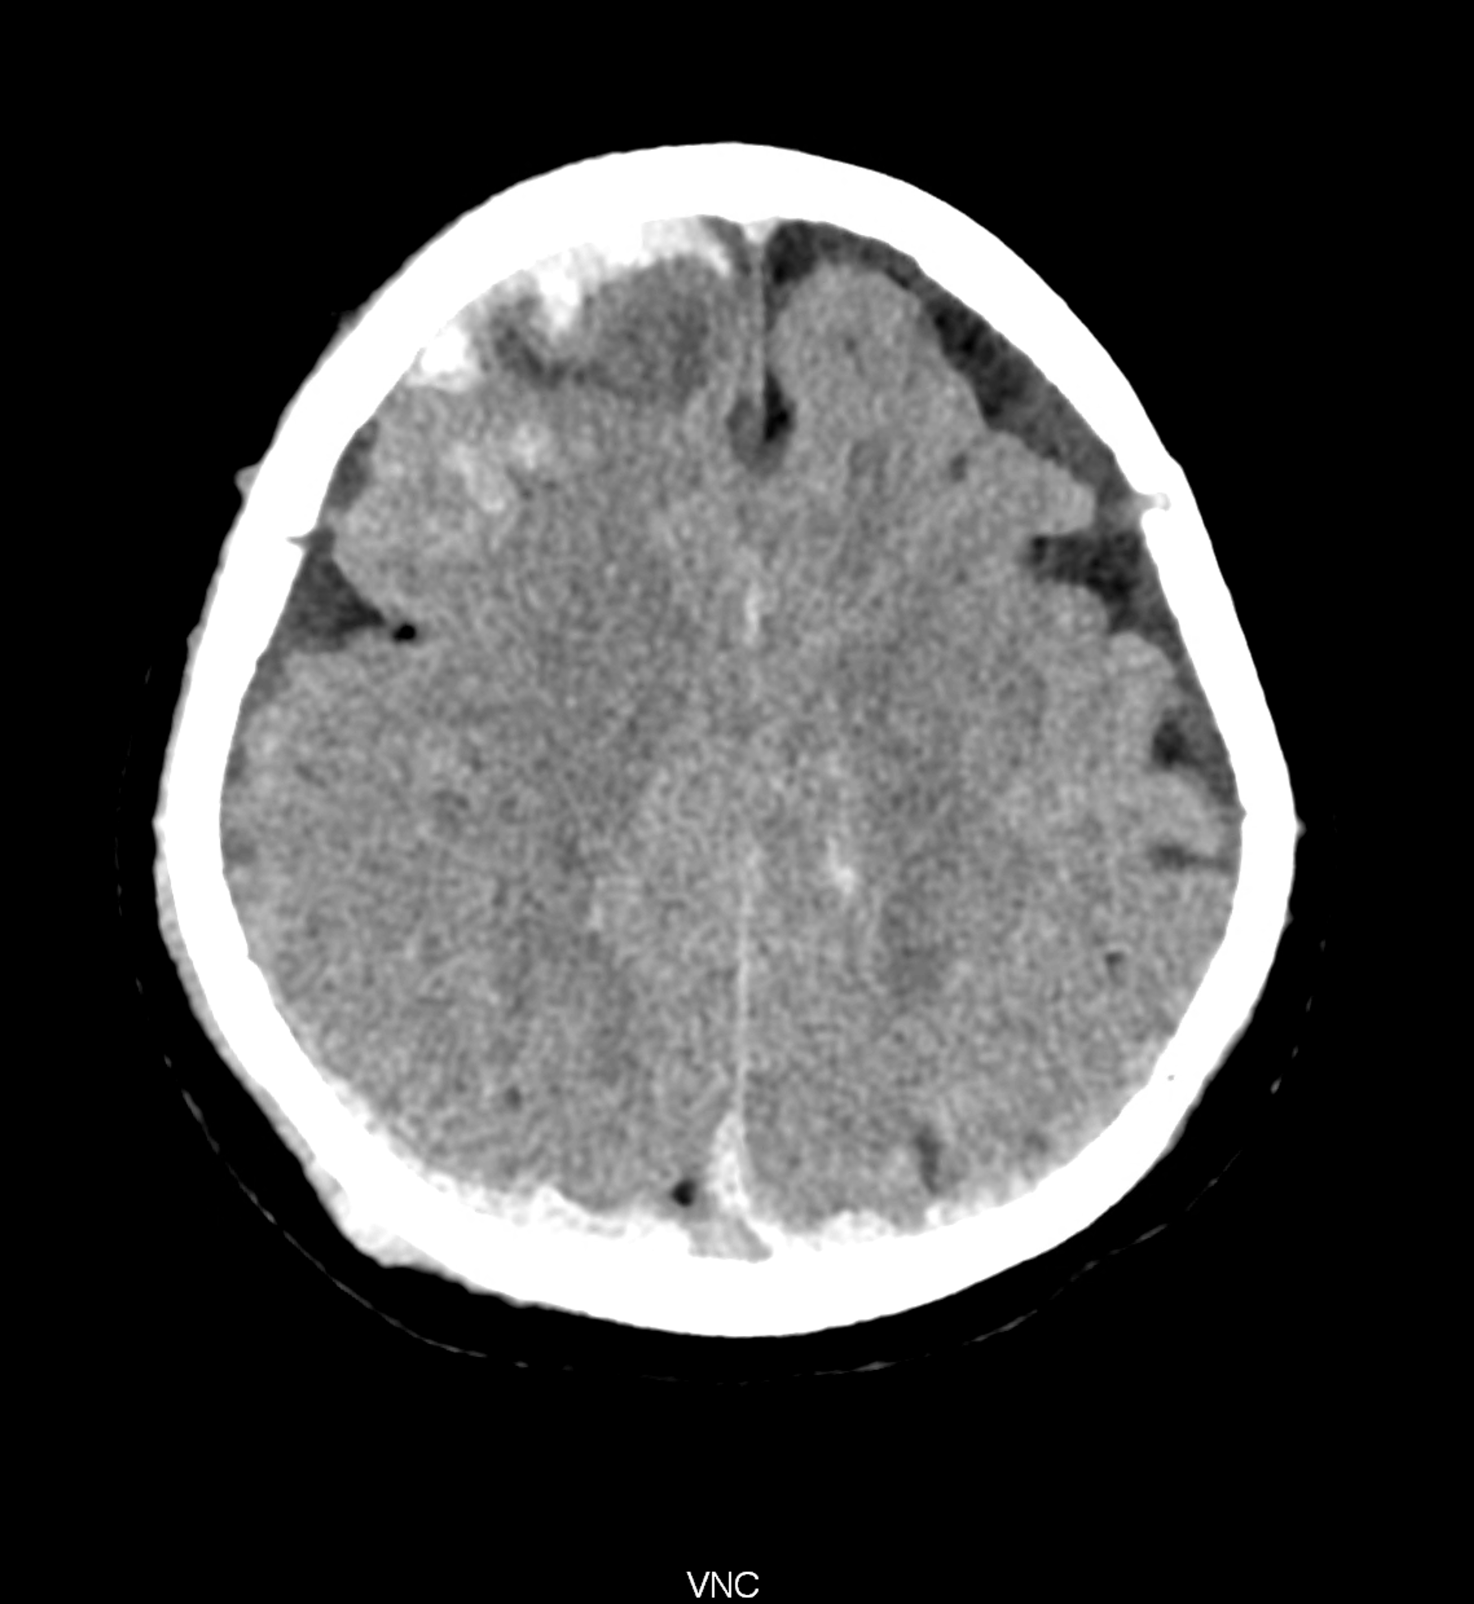

An example of the use of spectral imaging in complex brain injury, where contusions, diffuse axonal injury, subarachnoid hemorrhage, subdural hemorrhage, and blood in the ventricular system are present.

comparison of the images with the energies of monoenergetic reconstructions 40 keV, 67 keV (standard conventional reconstruction), 190 keV and virtual non contrast (VNC)